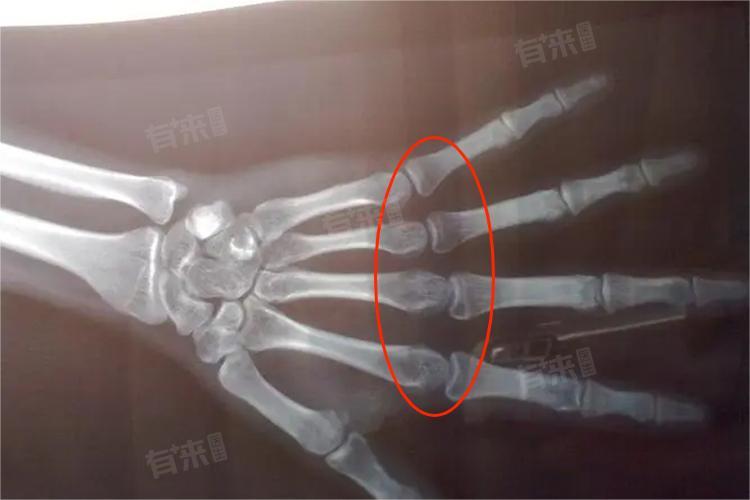

- 人体各部位的骨骺闭合时间并非同步,手部和腕部的骨骺相对较早闭合,临床上常通过拍摄手部X线片,观察腕骨、掌骨、指骨骨骺的骨化程度来评估骨龄,这对于判断儿童生长发育状况具有重要意义。而下肢长骨如股骨、胫骨的骨骺闭合时间相对较晚,尤其是股骨远端和胫骨近端骨骺,在青春期后期仍持续发挥生长作用,直至接近成年时才完全闭合。

1、X线检查:是评估骨骺发育最常用的方法,通过拍摄手部、腕部、膝关节等部位的X线片,能直观观察骨骺形态、大小及骨化程度,判断骨龄是否与实际年龄相符,进而分析骨骺发育有无提前或延迟。